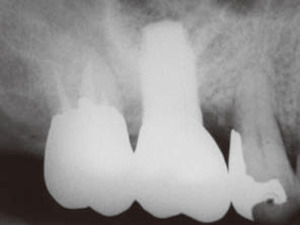

造骨手術例

造骨手術の手技は分類すれば多数ありますが、当院で行っている代表的なものをご紹介します。

●GBR

骨が不足している箇所を特殊な膜で覆い、骨のもととなる素材を詰めていき、骨の再生を促します。骨の吸収の度合いによって、その日にインプラントを埋め込むか、後日インプラント手術をするかを決定します。